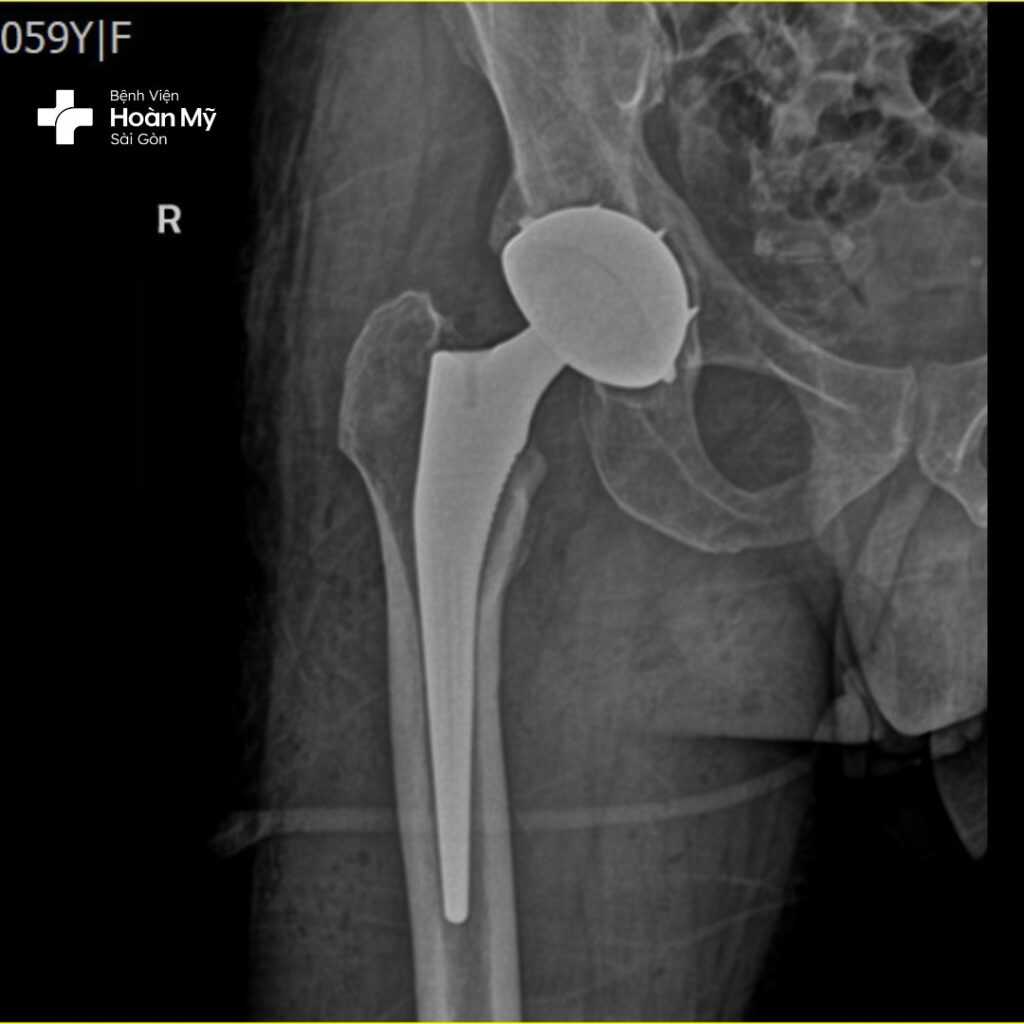

Hình ảnh X-quang trước khi phẫu thuật của ông Đ.

Chia sẻ về ca phẫu thuật, ThS.BS. Nguyễn Tấn Lãm – Trưởng Khoa Chấn thương chỉnh hình cho biết “bệnh nhân D. bị hoại tử cả 2 chỏm xương đùi trái và phải khá nặng. Kết quả chụp X quang cho thấy bệnh nhân bị hoại tử ở giai đoạn IV -V. Nếu phẫu thuật lần lượt từng chân thì bệnh nhân sẽ phải trải qua 2 cuộc phẫu thuật lớn. Đó sẽ là một trải nghiệm không hề dễ chịu”